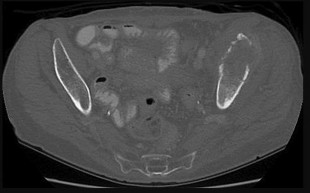

Figures 12a and 12b are a recent radiograph and a whole-body bone scan of an 81-year-old man who has hip pain and difficulty walking. His medical history is significant for obesity, hypertension, chronic kidney disease, and coronary artery disease. An examination demonstrates

moderate tenderness with passive range of motion of the left hip and an inability to actively flex the left hip against gravity. What is the best next step?

This patient has no known history of active malignancy. The radiograph shows a lesser trochanteric avulsion fracture (a fracture routinely associated with an underlying neoplasm). The bone scan reveals no other bone lesions. The femur fracture is statistically most likely to occur because of metastatic disease, but, without other evidence of metastasis, a primary bone sarcoma is possible, and biopsy is recommended before surgical fixation. Observation of this fracture, which is pathognomonic for neoplastic disease, is strongly discouraged.